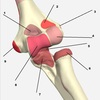

3

4

5

Perfectly

15

Q

2